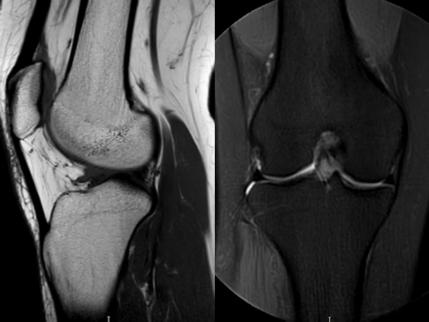

3. 上下樓“針刺痛”——軟骨的“磨砂紙預(yù)警”

場景:爬樓梯時膝蓋刺痛,久坐后僵硬如“生銹齒輪”

MRI偵查:發(fā)現(xiàn)軟骨變薄、缺損(早期骨關(guān)節(jié)炎信號),趕在“路面塌方”前修復(fù)

(軟骨損傷)